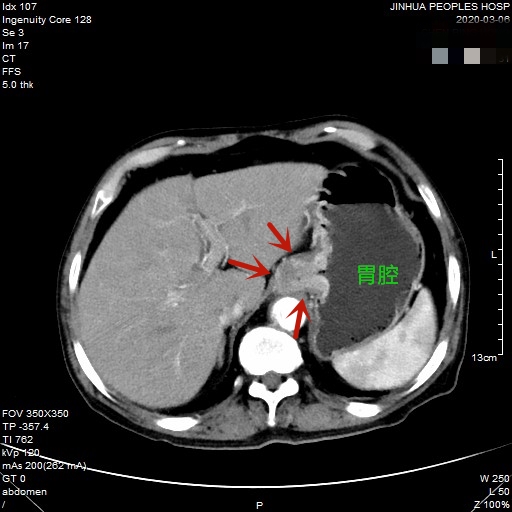

医生予以进一步检查CT增强发现肿瘤倒是没有明显侵犯周围脏器或结构,请我去会诊后,仔细阅片,发现从影像上看还是能够根治性切除的。所以转来胸外科拟进一步行手术治疗。下面是其CT增强的图像:

以上图片红色箭头所指处为贲门部肿瘤